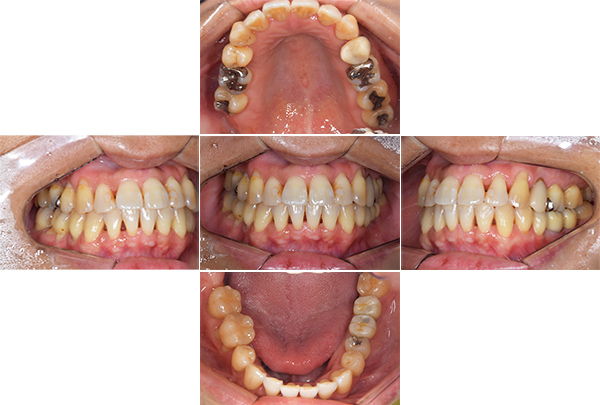

| 年齢・性別 | 63歳・男性 |

|---|---|

| 主訴 | インプラントがしたい |

| 治療内容 | オールオン4(上顎) |

| 治療費 | オペ料金(仮歯・薬代金含み)150万円+上部構造 (ハイブリットセラミック)150万円=計300万円(消費税別) |

| 治療期間 | 7ヶ月 |

| リスク・副作用 | 治療後の口腔管理が不適切な場合、インプラント周囲に炎症が生じインプラントが脱落する恐れがある。 |

審美的にも、機能的にも調和がとれており何よりも食べ物がちゃんとかめると言う事に感激されておりました。

今後定期検診をしながら経過を診て行きたいと思い

ます。